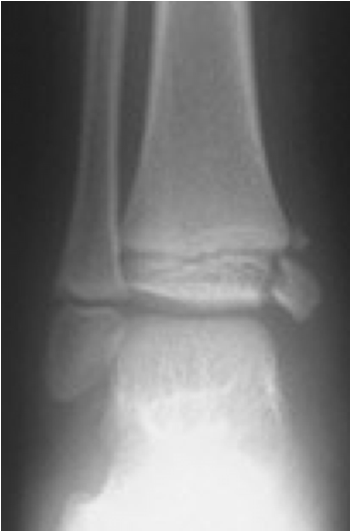

Fig. 11. Growth plate fracture with involvement of metaphysis and epiphyis (Salter-Harris type IV.